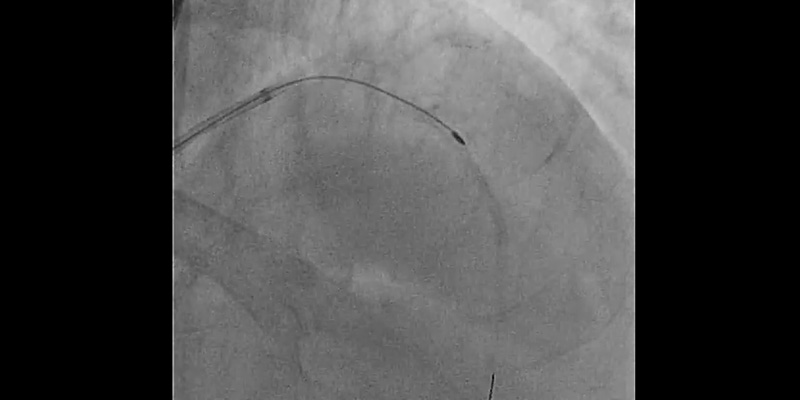

• Complication management strategy: A “Ping-Pong” technique was performed. The LM was engaged with a 6F radial EBU guiding catheter, while pulling back the 7Fr catheter a few centimetres. A hydrophilic wire was placed in the distal LAD parallel to the rotablator catheter and sequential dilatations with 1.2mm and 2.0mm balloons were performed at the site where the burr was trapped. This dislodged the burr, allowing it to be easily withdrawn.

• 2nd Rotational atherectomy with a 1.25mm burr: RotawireTM was placed again through the 6Fr radial catheter and rotablation was performed with a new 1.25 mm burr. Multiple runs were completed until there was no resistance through the lesion or drop in RPM.